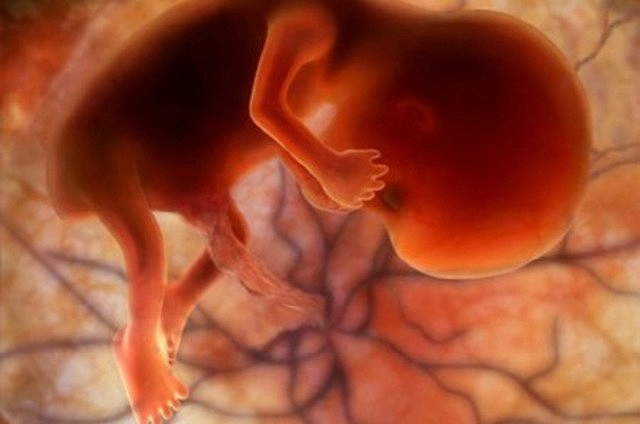

Se hacen visibles las yemas de brazos, la placa de la mano y la extremidad inferior en forma de pala. El cerebro se transforma en cinco áreas y algunos nervios craneales son visibles.Alrededor de esta semana, el embrión se convierte en feto, en esta fase, los tejidos y órganos formados durante el periodo embrionario comienzan a madurar, el esqueleto comienza a tomar forma, al igual que el cordón umbilical comienza a ensancharse.

• Octava semana

Octava semana

Alrededor de esta semana, el embrión se convierte en feto, en esta fase, los tejidos y órganos formados durante el periodo embrionario comienzan a madurar, el esqueleto comienza a tomar forma, al igual que el cordón umbilical comienza a ensancharse.

Mide entre 13 y 19 mm, los oídos, los dedos y la médula espinal se pueden observar, y las vértebras y costillas comienzan a desarrollarse. Se inicia el crecimiento de todos los músculos del cuerpo.